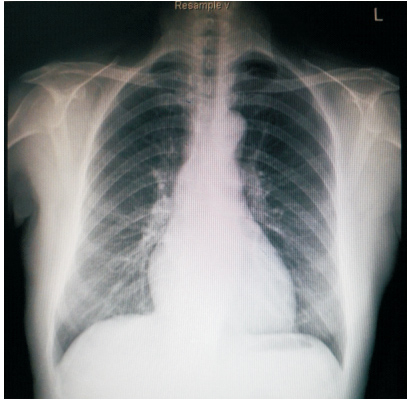

患者59岁,女性,因“发现心脏杂音3个月”于2011年1月份入院。患者2001年因下腔静脉狭窄于外院行下腔静脉支架植入术(支架厂家及型号不详),术后服用培达3个月后停药,无不适。2007年间断出现心悸及胸闷,未诊治。2011年单位体检发现心脏杂音,外院超声提示下腔静脉支架移位至右房,主动脉窦右房瘘。既往:体键。入院查体:血压120/70 mmHg(1 mmHg=0.133 kPa),心律齐,主动脉瓣第一听诊区可闻及Ⅲ/6级收缩期杂音,腹软,无压痛,双下肢不肿。入院诊断:下腔静脉狭窄,下腔静脉支架植入术后,下腔静脉支架移位,主动脉窦右房瘘。入院后相关检查:超声心动图:LV 53 mm,EF 74%,主动脉右冠窦与右房间探及破口约3~4 mm,下腔静脉入右房口处探及支架回声,支架突入右房约20 mm;胸片(图 1、2):侧位片金属支架结构影不连续,心影区偏前区可见线状高密度影。CT(图 3、4):右室游离壁、间隔壁、三尖瓣口、右房、下腔静脉近心段可见支架金属丝影。冠状动脉造影检查(图 5、6):冠状动脉未见明显异常,可见支架影随着心脏的跳动位置发生变化。